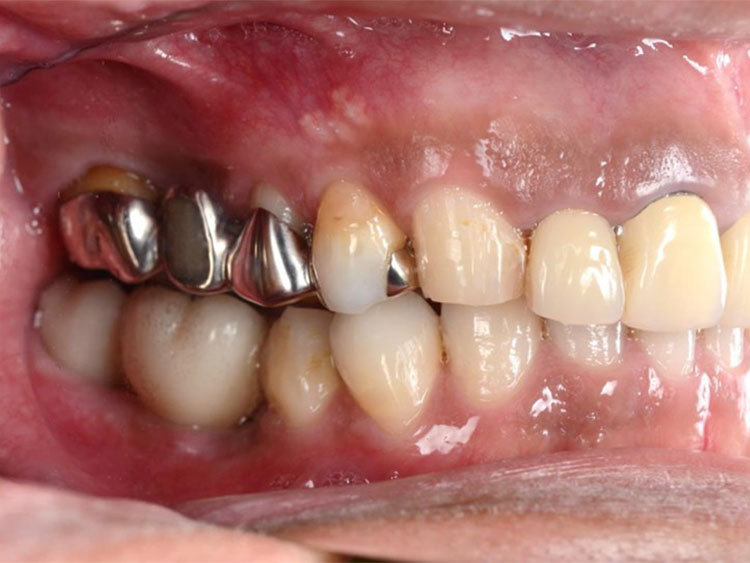

インプラント症例 Case1

Treatment cases

Before

After